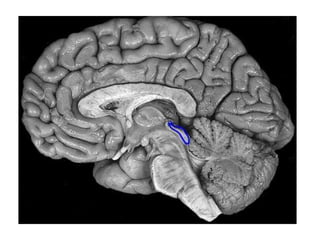

A-Genu of the

Corpus Callosum

B-Anterior Horn of

the Lateral Ventricle

C-Internal Capsule

D-Thalamus

E-Pineal Gland

F-Choroid Plexus

G-Straight Sinus

Axial view

1-Pineal gland

2-Habenula

3-3rd ventricle

4-Pulvinar

5-Lateral ventricle

Coronal View

1 Pineal gland

2Lateral ventricle

3-Corpus callosum

4-Fornix

5 Thalamus

6Middle cerebellar

peduncle

Sagittal View

1Posterior

commissure

2Cerebral aqueduct

(of Sylvius)

3 Tectum

4Fourth ventricle

5-Cerebellum

6Quadrigeminal

cistern

7 Pineal gland

8Splenium , corpus

callosum

9 Third ventricle